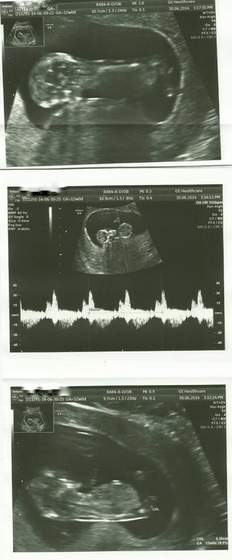

dziękuję :) wychodzi na to, że jest ok, chociaż jeszcze nie można policzyć paluszków... u rąk będziemy liczyć w 20 tygodniu, a u nóżek w ogóle nie damy rady... tylko czy kończyny są prawidłowe (szpakowatość itp). Mam nadzieję,że jakby co to Mała będzie miała za dużo paluszków, tak jak Antoś. Bo zawsze łatwiej uciąć niż dokleić ;)

usg.jpg

Nasze małe maleństwo :))